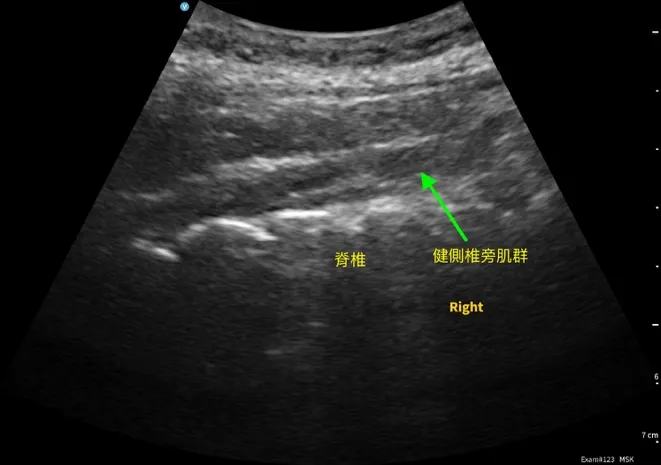

我使用超音波由頸部前外側向後檢查椎間盤健康狀態,看到 C5/6/7 段椎間盤變扁,並伴隨小鈣化訊號。 再往頸部側邊掃描,在神經根出口附近,探頭輕壓就能誘發她熟悉的痠痛與痠麻。 同時在頸部後側椎旁肌群,與健側比較,下段也呈現明顯纖維化與脂肪浸潤樣態。

這些發現讓我判斷:除了椎間盤本身,神經根出口周邊的高張力與沾黏軟組織很可能是讓症狀被持續放大的關鍵。

- 超音波線索:C5/6/7 段退變相關訊號;神經根出口附近輕壓可誘發熟悉痠麻;下段椎旁肌結構改變(纖維化/脂肪浸潤樣態)。